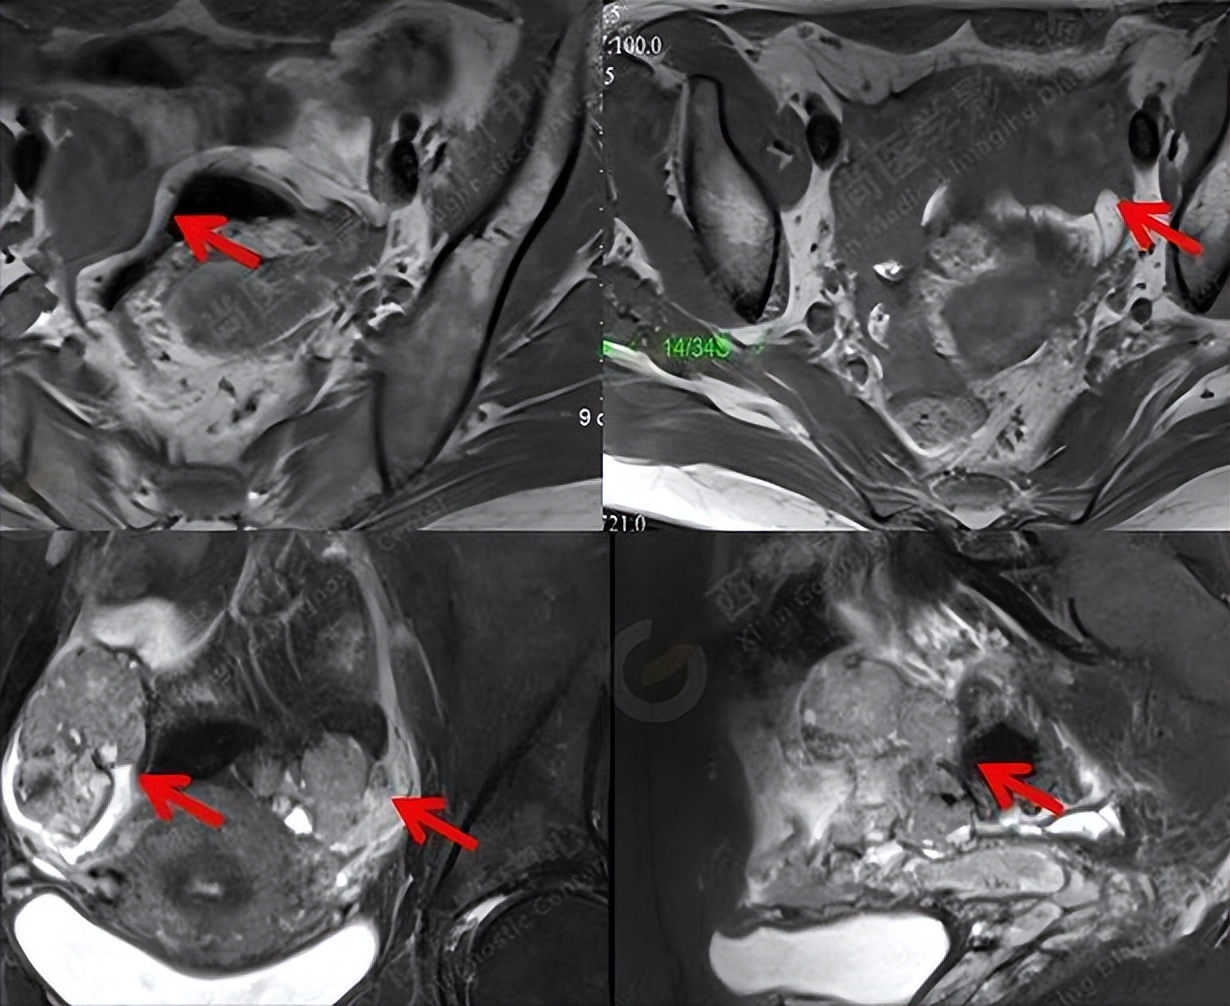

6.乳头状突起

良性肿瘤没有乳头状突起,或者有少量小突起。而恶性肿瘤常见多于4个以上的呈簇状分布的不规则乳头状和菜花状凸起且血供丰富。

总结:有乳头状突起,可能是良性也可能是恶性,但若是有4个以上不规则乳头状和菜花状突起,则多见于卵巢恶性肿瘤。